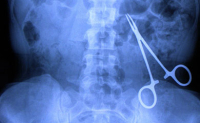

Les plaies pénétrantes par objet inerte constituent une situation fréquente en pratique médicale, pouvant engager le pronostic fonctionnel, voire vital, en fonction de leur localisation et de la qualité de leur prise en charge initiale. Une évaluation rigoureuse et une prise en charge précoce sont essentielles afin de prévenir les complications, notamment infectieuses, vasculaires ou nerveuses. Toutefois, des erreurs diagnostiques ou thérapeutiques peuvent survenir, exposant le patient à une évolution défavorable.